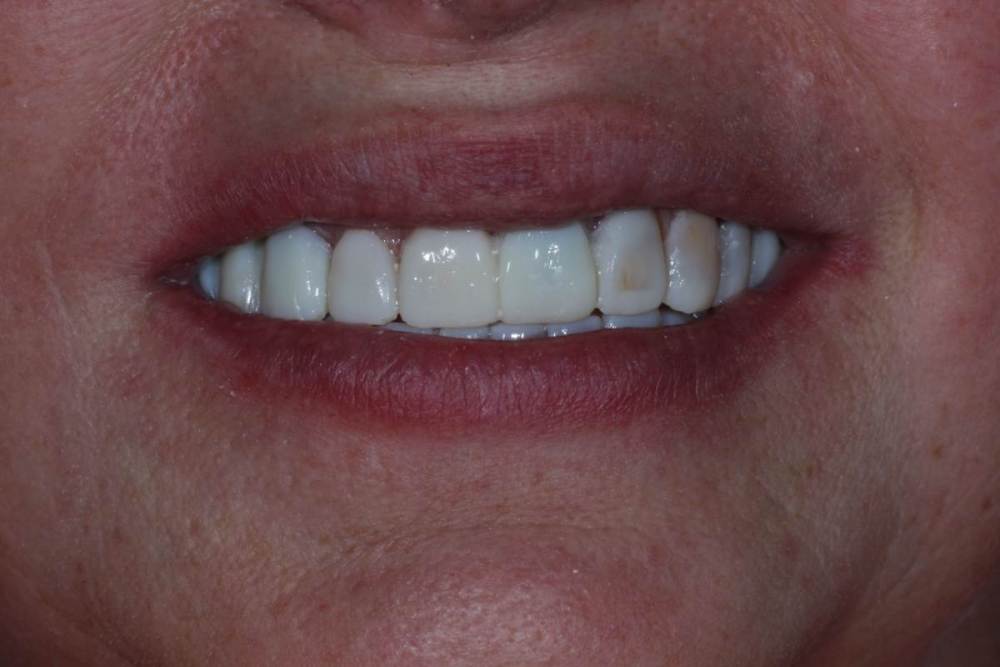

Улыбка до:

IMG_0634.thumb.jpg.5ffaa548d0888778b0f37eea7c1e219e.jpg

Улыбка после(стоит анестезия, на губу не обращаем внимания):

464983353_IMG_0833(2).thumb.JPG.6fc1756f43caeb2ff7b9787b9c74bee1.JPG

Перенос был без препарирования передних зубов, поэтому пациент оценивает только форму и функцию. На цвет не обращаем внимания.